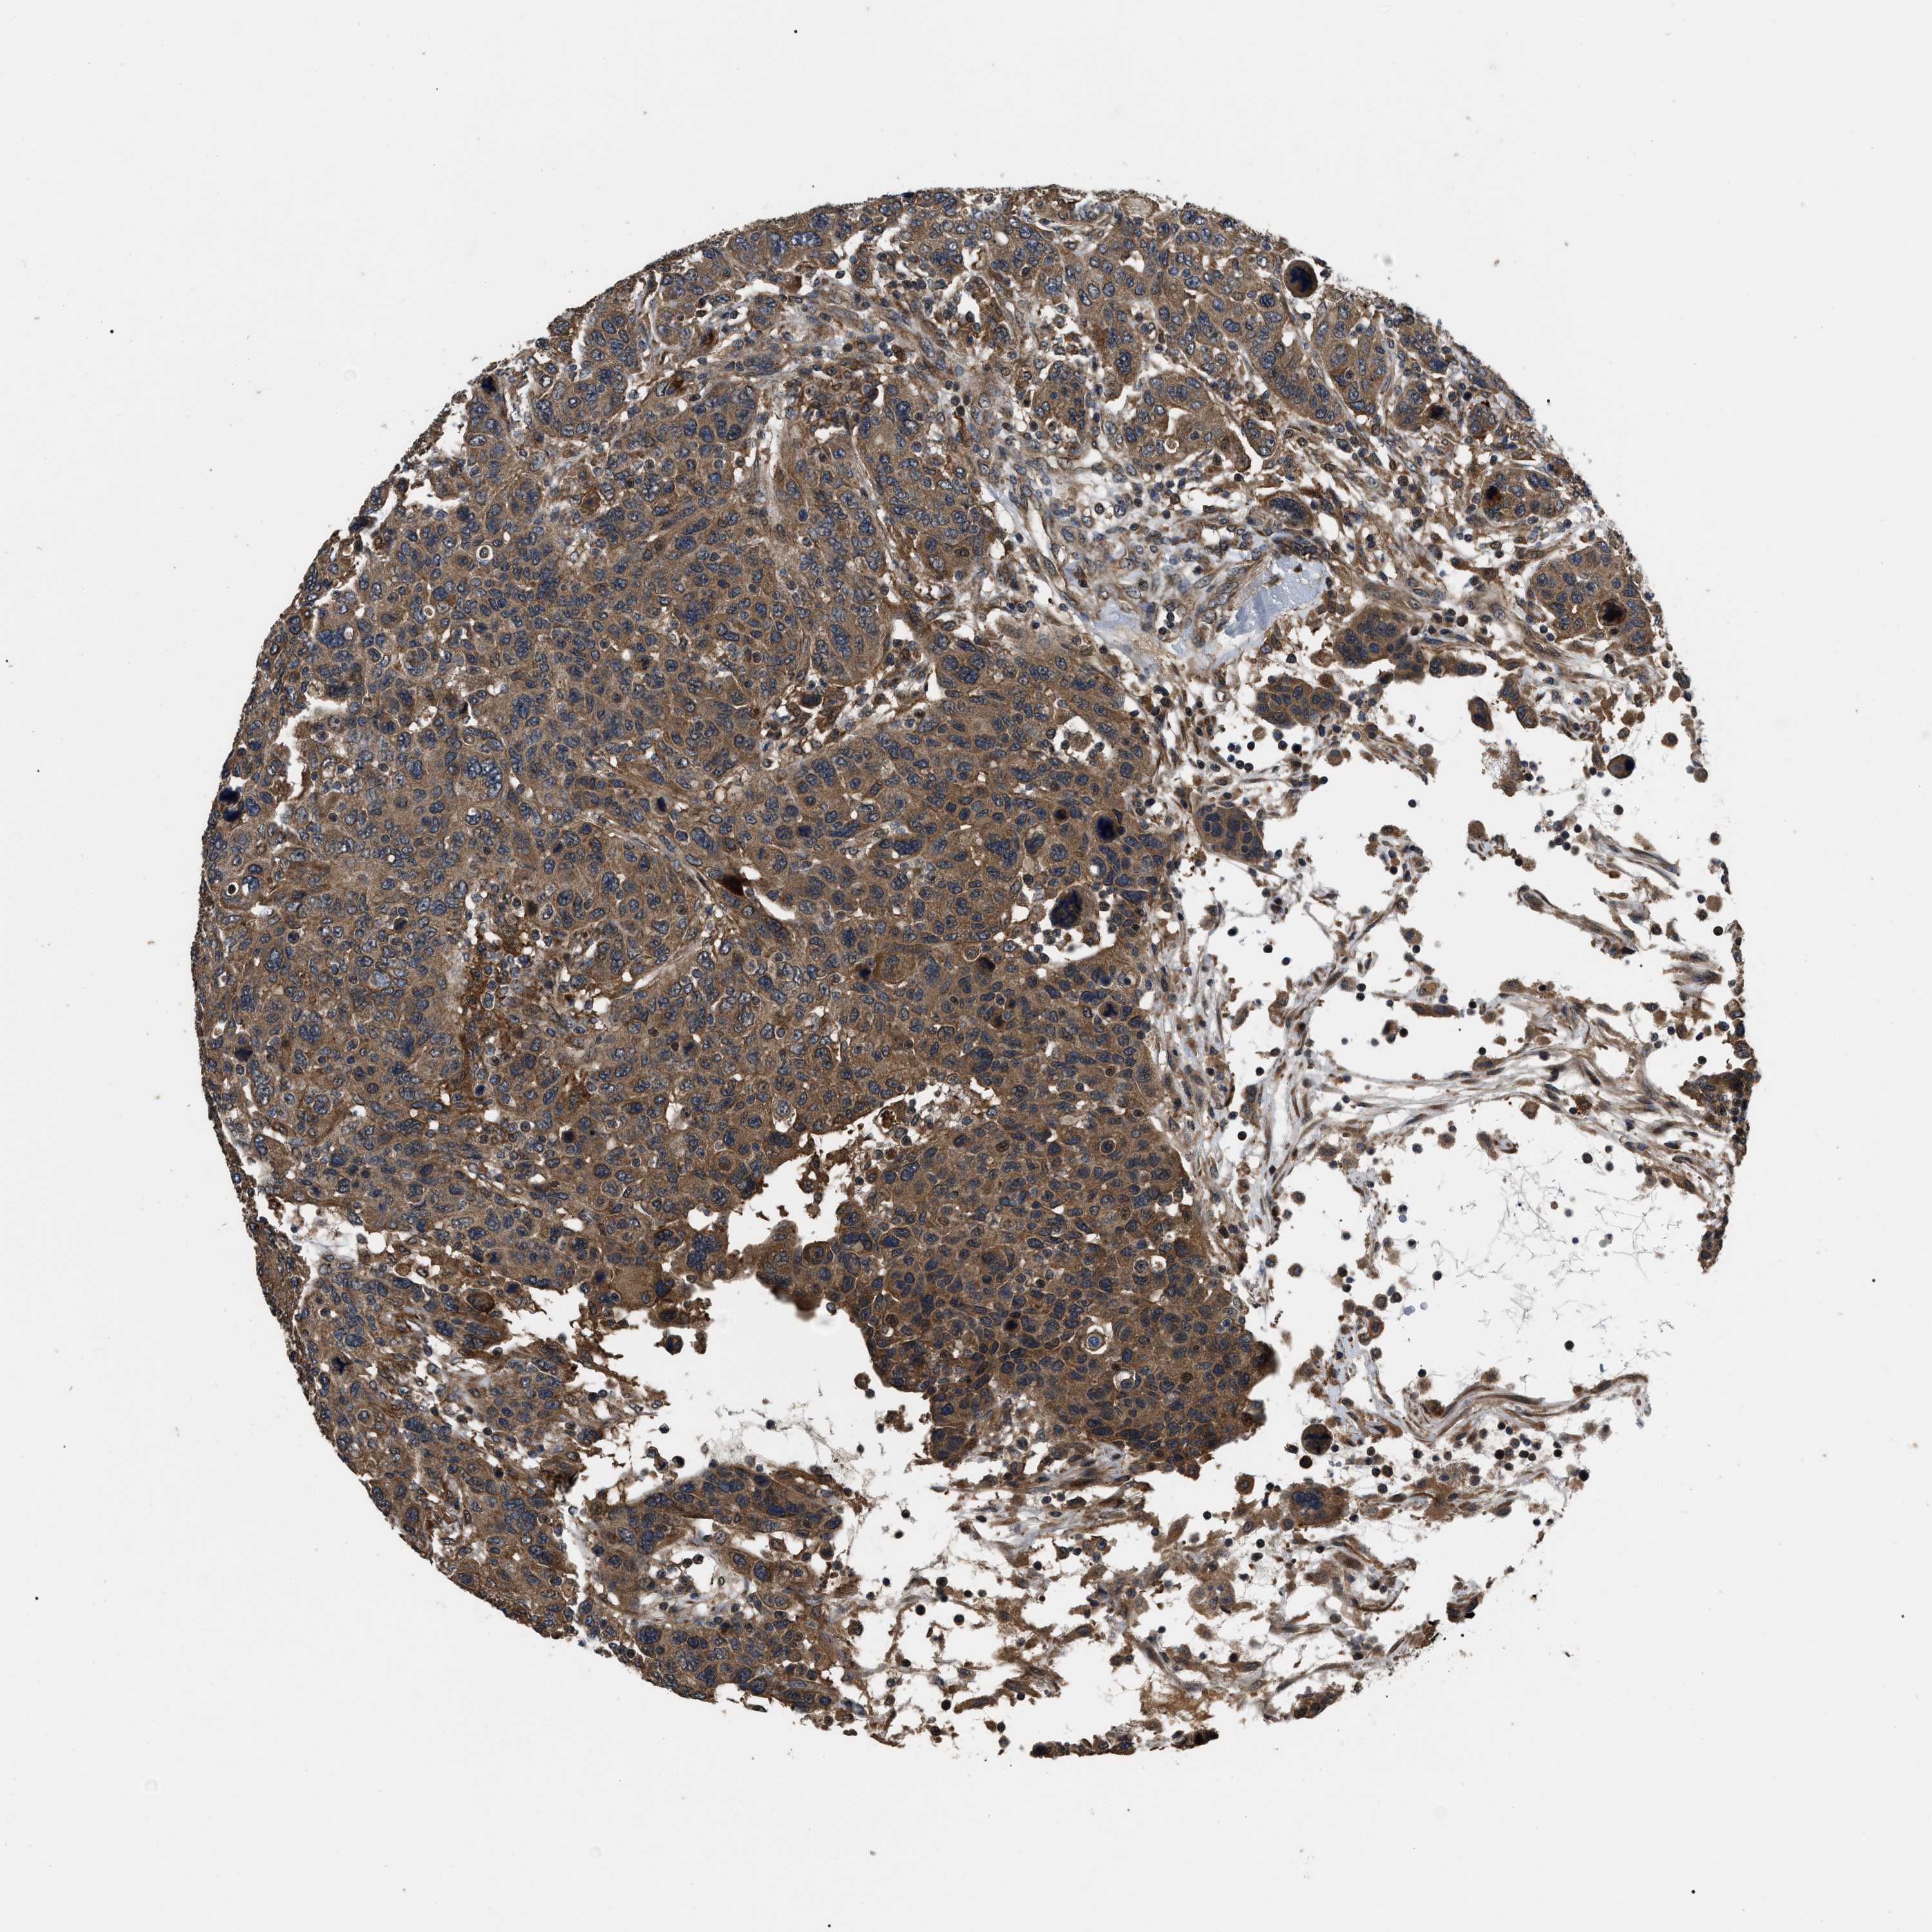

CANCER BREAST CANCER Show tissue menu

BRCA TCGA BRCA VALIDATION PROTEIN EXPRESSION